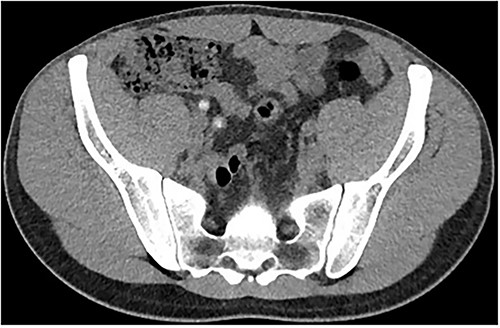

Two days following stent removal, the patient developed acute onset right lower quadrant and flank pain. A non-contrast CT of the renal tract was obtained to assess for procedure or stone-related complications. The scan demonstrated two distinct retained stones within the proximal right ureter, with associated moderate ureteronephrosis. Additionally, within the right lower quadrant of the abdomen, a radiopaque vermiform entity was demonstrated (Figs 1–3). This entity was not pathological, however, represented a normal appendix that had, consequent to contrast administration during a urological procedure, become filled with contrast secondary to vicarious contrast excretion.

Coronal imaging, demonstrating contrast-filled vermiform structure.